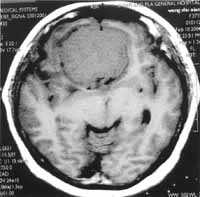

锁孔手术应注意其适应证的掌握,肿瘤的大小不是手术的绝对适应证或禁忌证,决定是否采用小切口技术主要是看肿瘤的血液供应情况[5]。本组切除的肿瘤最大径达12cm,其中有脑膜瘤(最大径8cm,见图1、图2)、听神经瘤和胶质瘤,只要肿瘤供血不是十分丰富,手术可以顺利完成。

图1 颅前窝脑膜瘤术前CT,肿瘤直径8cm